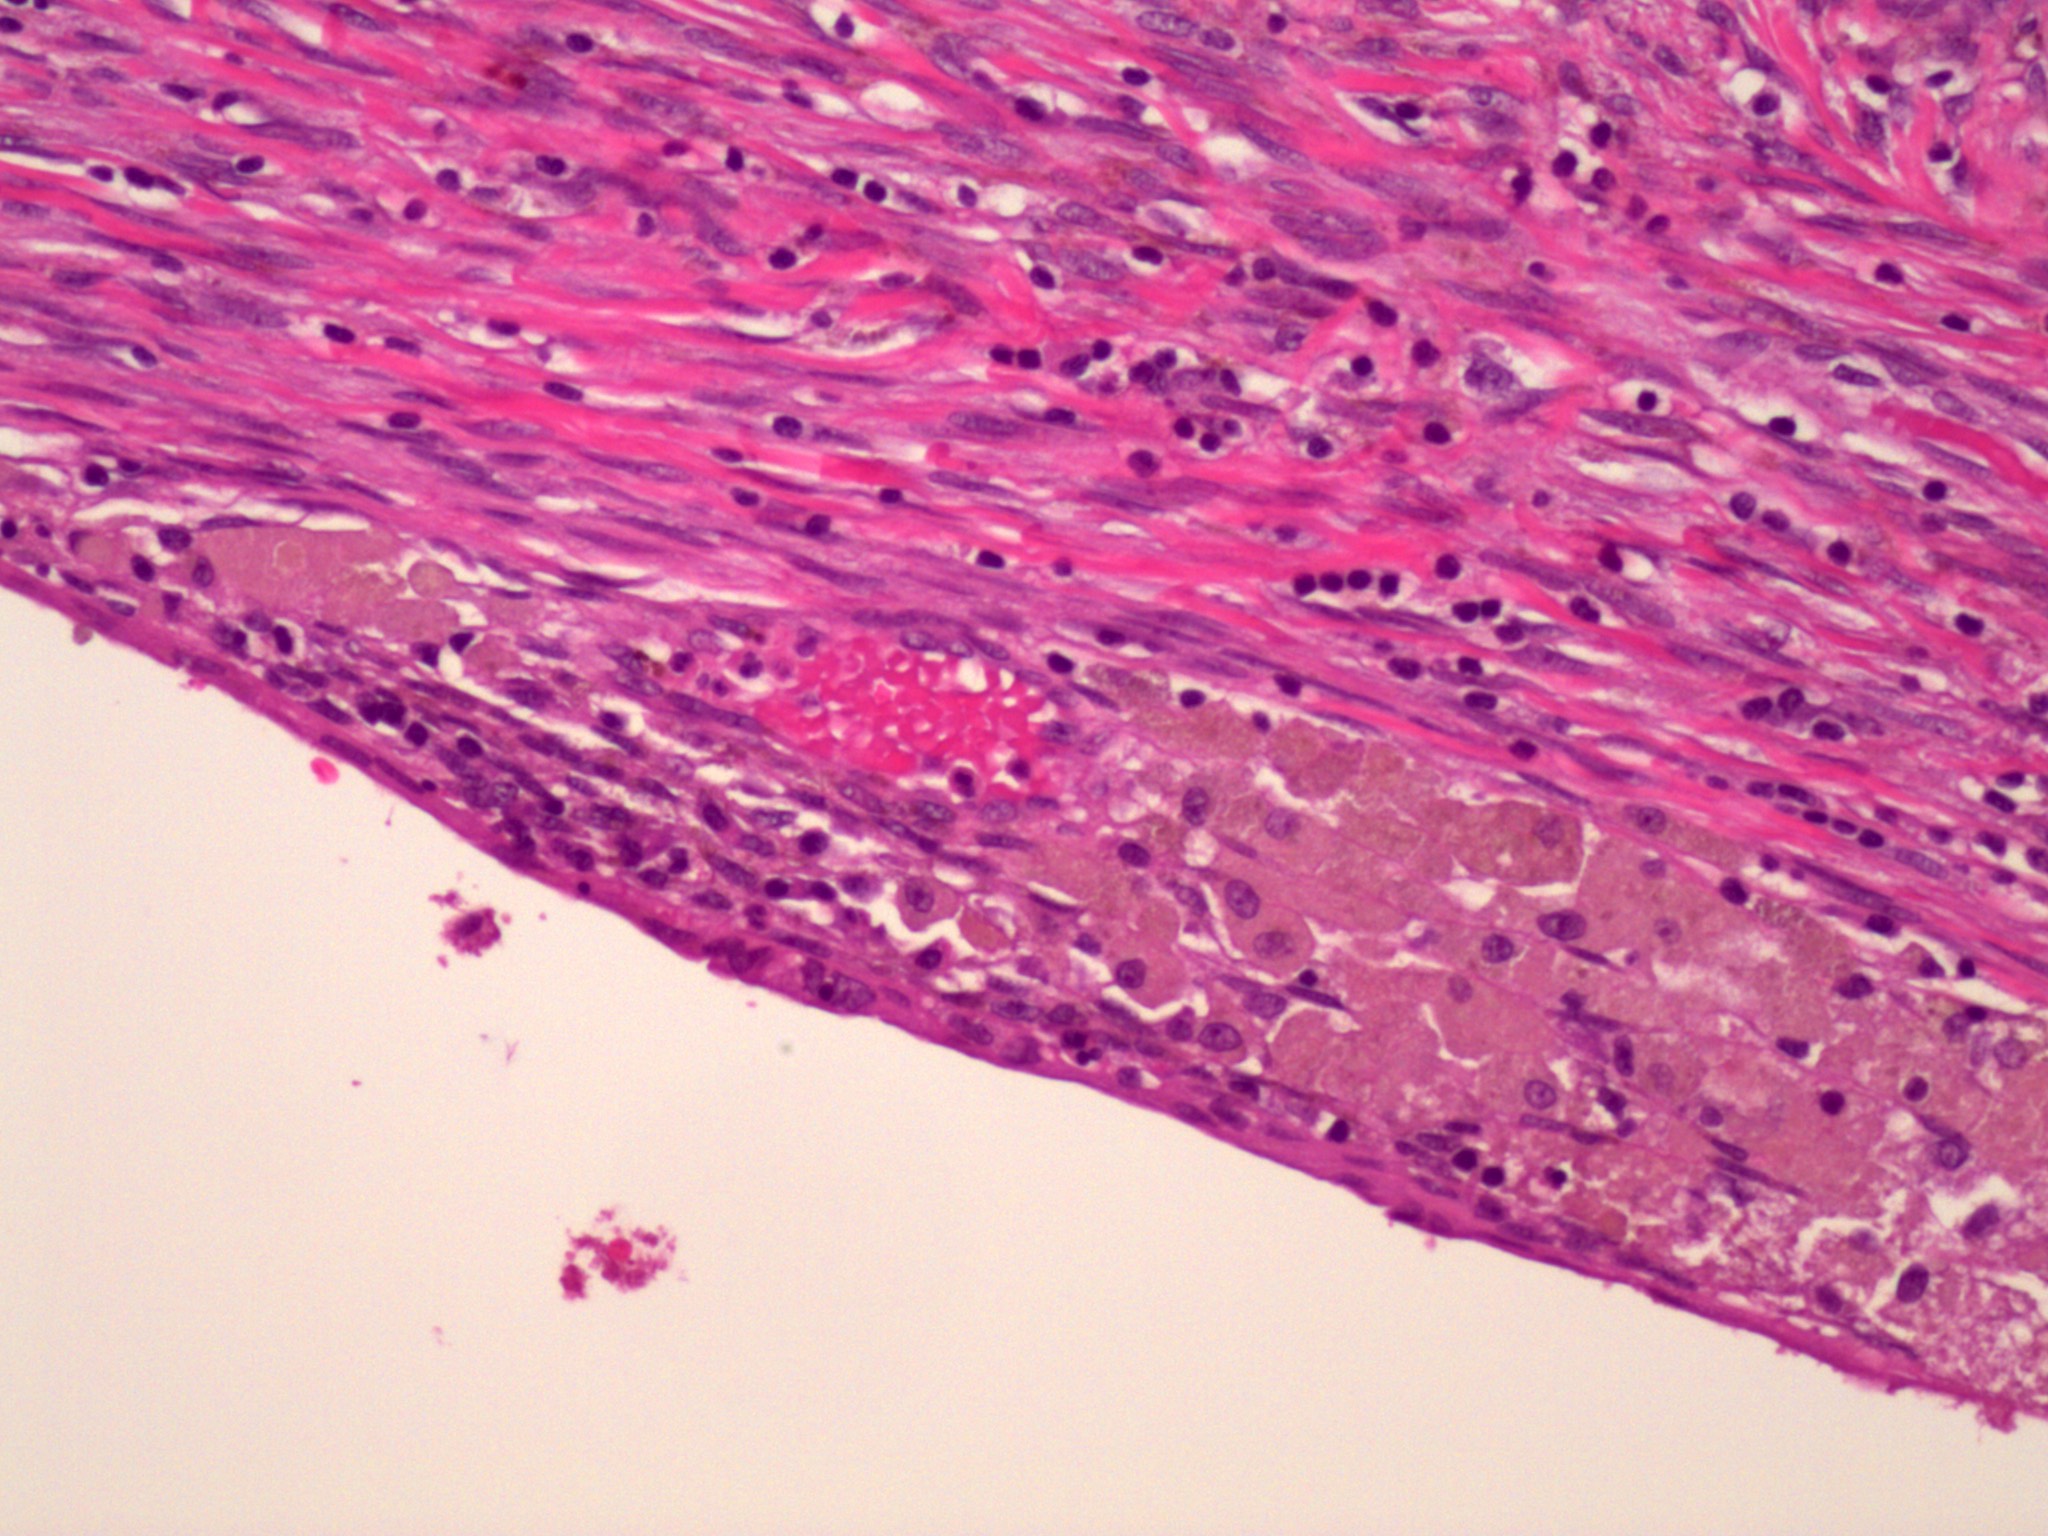

Microscopic (histologic) images

Microscopic (histologic) description

- Endometrial type stroma

- Often contains fine capillary network

- May undergo smooth muscle metaplasia, fibrosis (longstanding), decidual change

- Stroma may be the only identifiable component (stromal endometriosis)

- Evidence of chronic hemorrhage (hemosiderin laden or foamy macrophages)